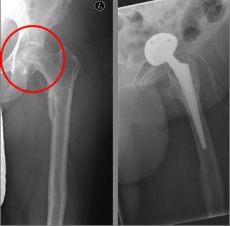

Pertrochanteric fractures, which are not femoral neck fractures close to the hip, are treated with a so-called gamma nail. The rupture here runs through the large and / or small "hillock" (trochanter major and minor) of the thighbone. Here, due to the location of the fracture, the blood supply to the femoral head is NOT compromised. After the operation, an immediate mobilization can take place under pain-adapted full load.

Picture: In this pertrochanteric femur fracture, a gamma nail was used to stabilize the fracture. The femoral head does not have to be replaced in this case, because the femoral neck is intact and the femoral head is still well supplied with blood.